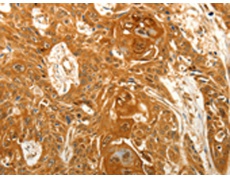

IHC positive control:

Human esophagus cancer

IHC Recommend dilution:

50-200